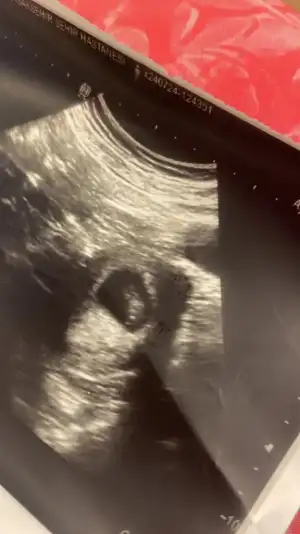

Gozun aydin canim, sana demistim Allahin izniyle birsey olmaz diye. Bana da doktorum nipt test onerdi. Yasim 37 ve kilolu gebeyim. Nerden bakarsan risk grubu malesef. Ama olsun rabbim yardimcimiz insallahÇok şükür bebekle ilgili bişey yokmuş herşey yolundakalbi 165 atıyor dedi doktor bebek çok sağlıklı dedi